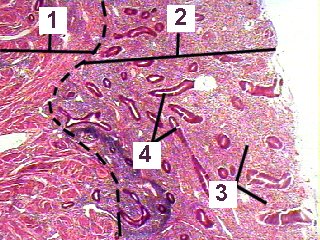

2. Endometrium

3. Ischaemic degenerating stroma

4. Degenerating glands

| Fig 88-004 | |

| This is a higher magnificaiton of a section through the endometrium during the menstrual phase. | |

1. Myometrium 2. Endometrium 3. Ischaemic degenerating stroma 4. Degenerating glands |